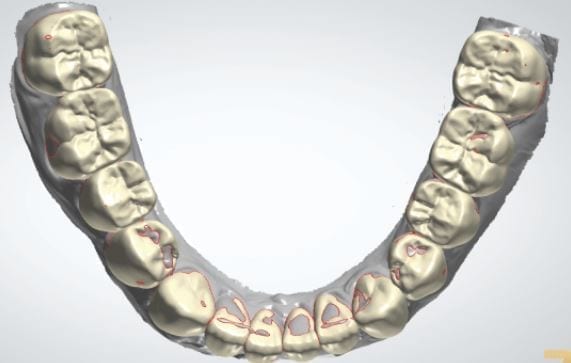

The digital models were then imported into a third party software where a library of tooth morphologies are available for the clinician to choose from.

Once the appropriate library is chosen, the digital wax ups are performed. In the subsequent photos you can see the transparent overlay of the wax-ups to the original position of the existing dentition

The case was designed by CADENT BESSA, and the models were printed by Burbank Dental Lab with Carbon Printers. There restorations were milled and cut back and layered by Burbank Dental Lab